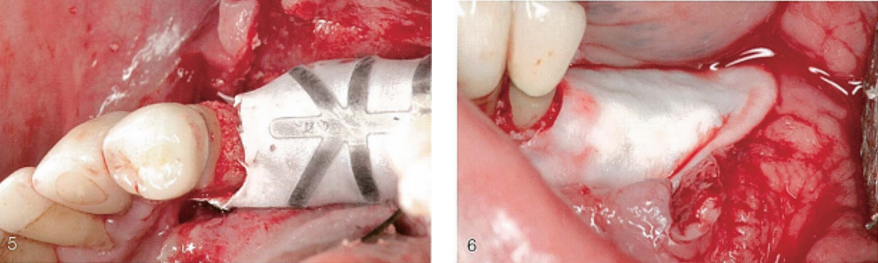

(3)颊侧观,植入混合植骨材料。(4)颊侧观,固定e-PTFE-TR膜。

(5)牙合面观,显示膜和天然牙之间的距离。

(6)颊侧观,天然胶原膜覆盖TR膜。胶原膜用来关闭TR膜和骨之间的缝隙。